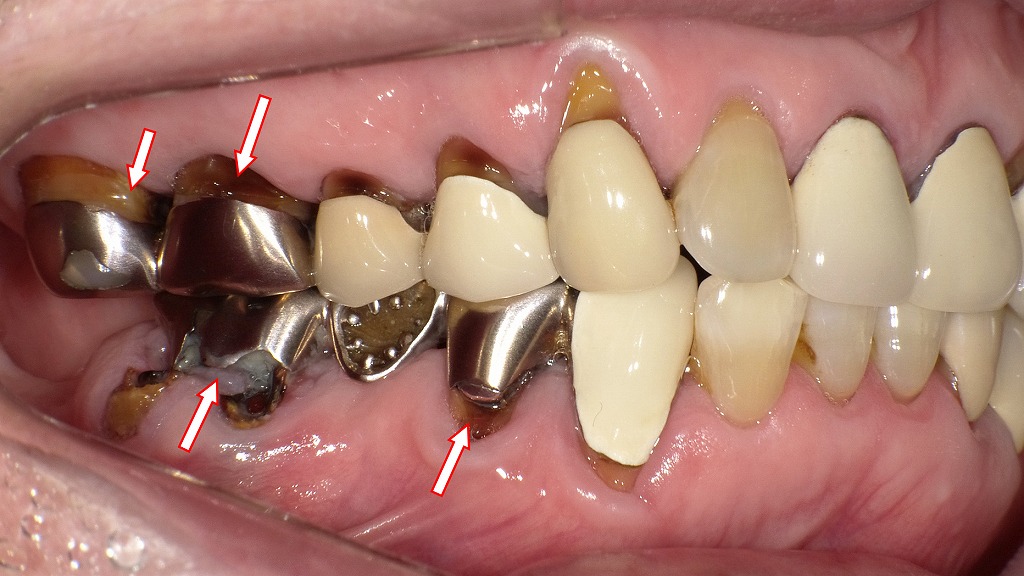

この画像は右側臼歯部(主に右下6番および右上6・7番)を中心とした口腔内写真です。以下に詳細を解説します。

金属冠(クラウン)やブリッジが装着された口腔内で、複数箇所に不適合や二次う蝕(再発虫歯)が見られる状態です。矢印部分に特に問題が集中しています。

■ 右下6番(下顎第一大臼歯)

- 歯頚部(歯と歯ぐきの境目)に虫歯あり。

- プラーク(歯垢)の蓄積が顕著で、歯肉の炎症リスクも高い。

- 不適合な金属冠と歯の境界から虫歯が進行している。

■ 右下4番(金属冠)

- 歯頚部と金属冠の間に明らかな隙間が認められる。

- その隙間に細菌や歯垢が入り込みやすく、二次カリエス(再発虫歯)のリスク大。

■ 右上6番・7番(金属冠)

- 金属冠と歯肉の境目にギャップ(段差)あり。

- 歯垢がたまりやすく、歯肉炎や口臭の原因になる。

- 清掃が困難なため、定期的な歯科メンテナンスが必要。

💨 臨床的な懸念点

- これらのギャップや不適合な修復物は、プラーク(歯垢)の停滞部位となる。

- その結果、虫歯・歯周病・口臭の原因になる。

- 金属冠の劣化や歯肉退縮により、適合不良が進行している可能性もある。

🩺 対応のポイント

- 不適合な冠の再製作(特に右下6番・右上6番7番)

- 歯肉縁下のプラークリスクを軽減するための精密な補綴再装着

- 定期的なプロフェッショナルクリーニング(PMTC)

- 必要に応じて口臭検査や歯周検査